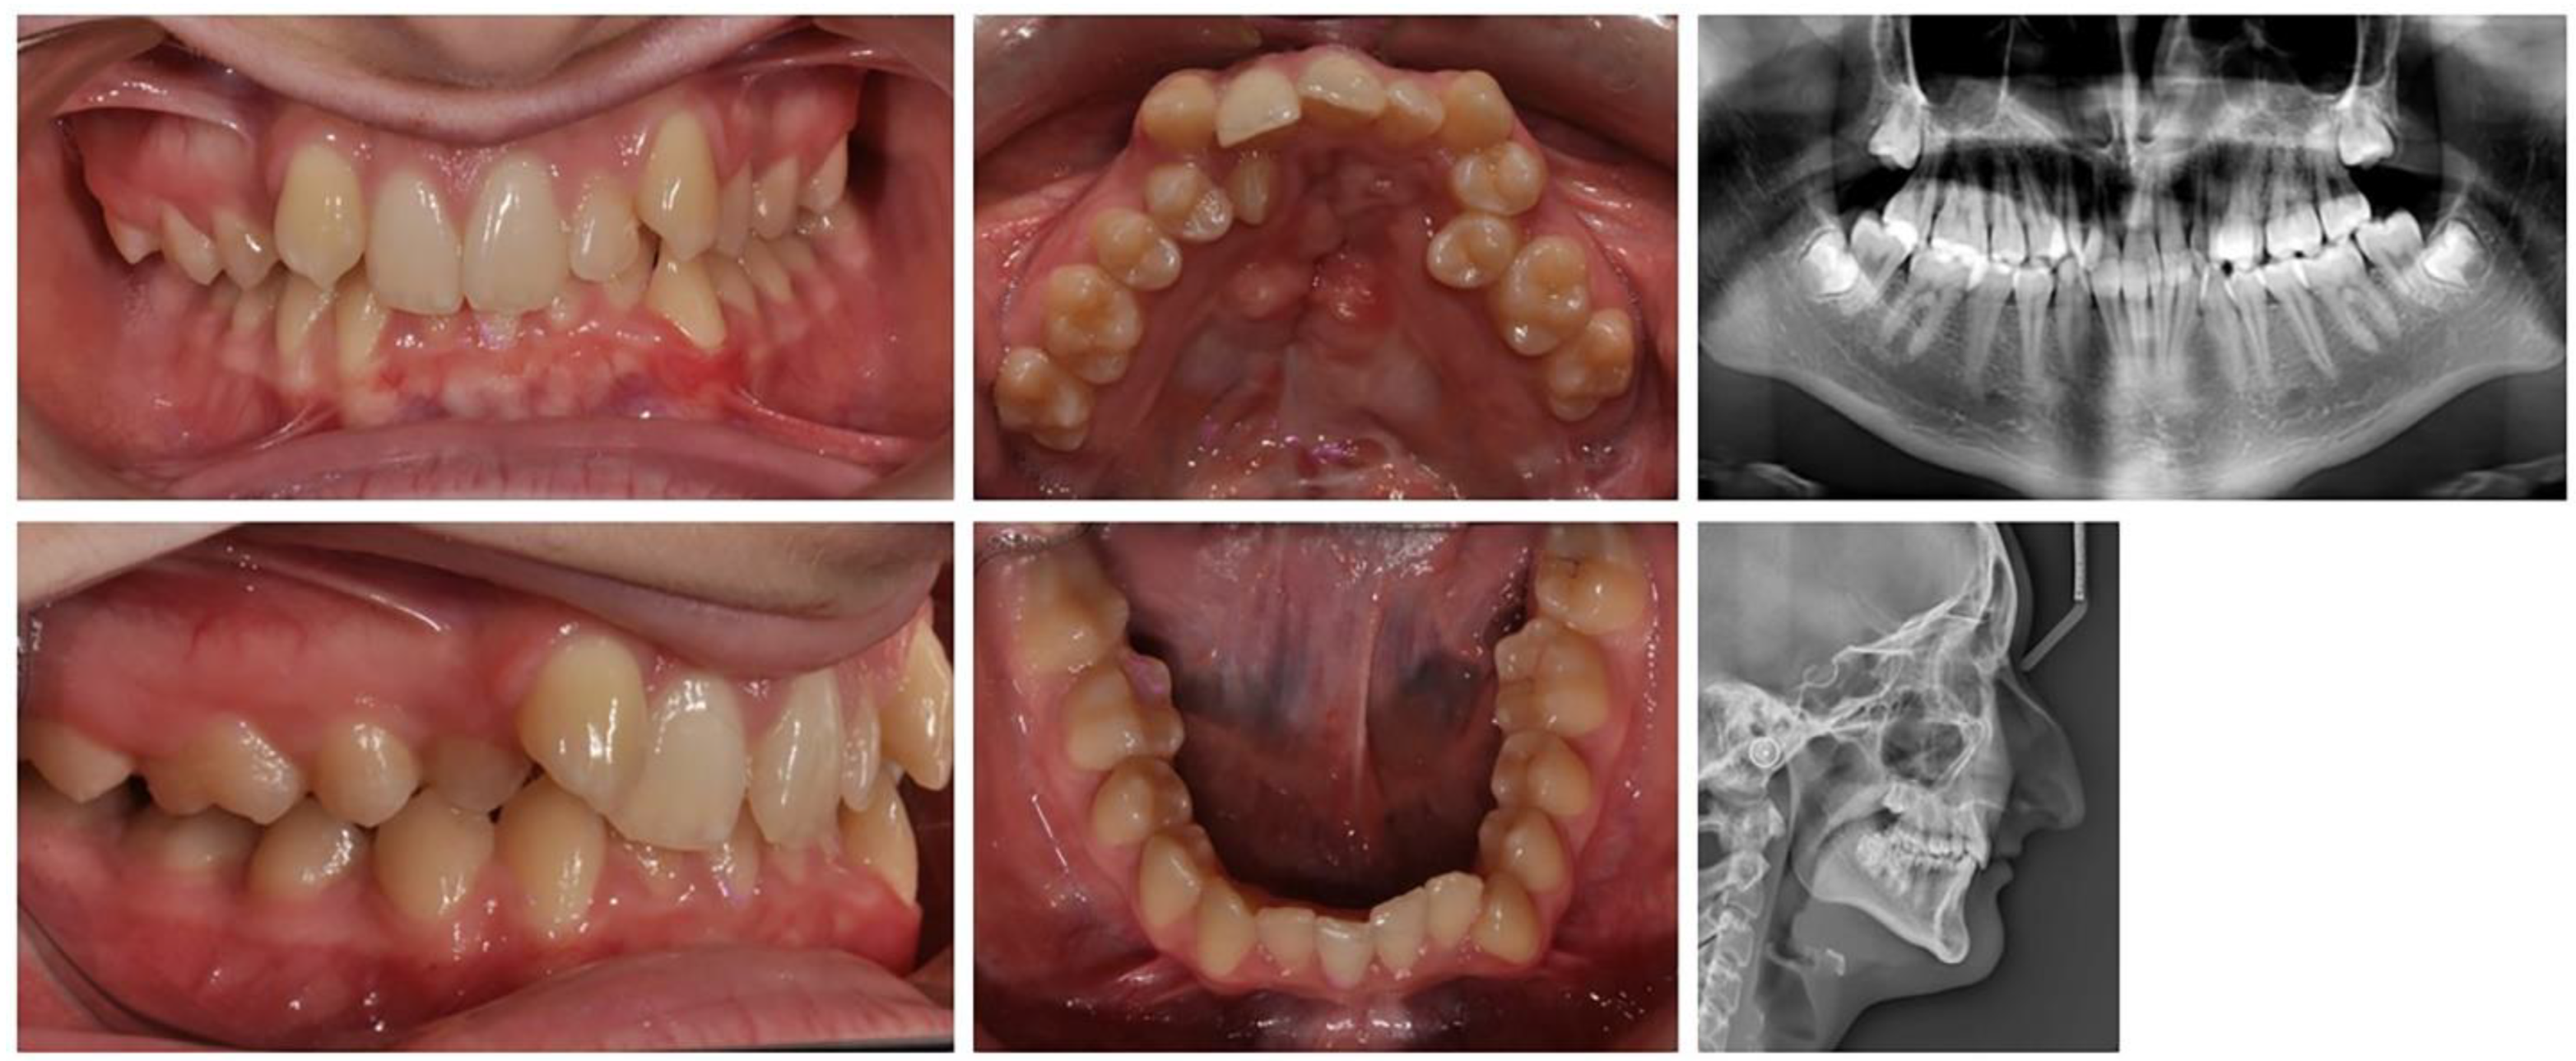

A 17-year-old female patient with a surgically repaired cleft of the hard palate was included. The patient’s complaint was worsened aesthetics. The upper frontal teeth were retruded and extruded; thus, the bite was deep. During the first clinical examination, a reduced perimeter of the upper dental arch was found, crowding was observed both in the frontal and in the middle segment (in the premolar area) and the shape of the dental arch was trapezoidal (Figure 6).

In orthodontic analysis, the count of medio-distal (MD) diameters of ten teeth from 15 to 25 was MD (15–25) = 63.9 mm. The dental arch perimeter was P (15–25) = 53.83 mm. The discrepancy of MD-P = 10.07 mm was observed (Figure 7). The treatment goal was to provide space in upper dental arch through the extraction of first premolars 14 and 24. The count of first premolar space was almost equal to the discrepancies in perimeter. The upper-right lateral incisor was located on the palate and that resulted in the canine being in contact with the central incisor. The lateral incisor should be included in the dental arch. During the distal movement of the canine, there was a risk of the medialisation of teeth in distal segment and of lost anchorage. Therefore, the use of PDaA was the appropriate decision.

For the purposes of orthodontic treatment, the extraction of two upper premolars (14 and 25) is required, which will provide a space exactly equal to the crowding size (the sizes of the right lateral and left premolar). It was not desirable to design a biomechanical system which would involve the medial displacement of the distal anchorage teeth, as this occurs with the classic distal displacement of canines and anchorage second premolar and first molar (anchorage type A). In this clinical case, a stable distal anchorage zone was required, which could be provided by mini-orthodontic implants or a rigid transpalatal arch involving all available anchorage teeth (Figure 8). When fabricating this type of digitally planned arch, elements were incorporated into its design to aid in a more bodily movement of the canines, which would reduce the inclination side effects of their movement.

Figure 6. Initial status of patient with a surgically repaired cleft of the hard palate.